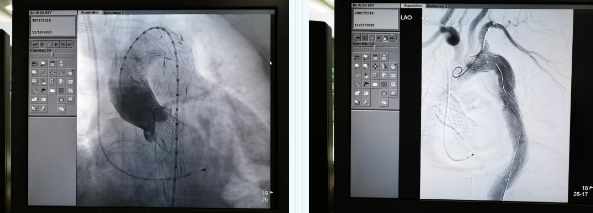

11月19日,西安國際醫(yī)學中心醫(yī)院心臟外科TAVR團隊在心臟病醫(yī)院張金洲副院長主持下,順利完成一例罕見“經(jīng)股經(jīng)導管主動脈瓣置換術 經(jīng)導管主動脈腔內隔絕術”。經(jīng)查閱文獻證實,此一站式復合手術國內尚未見報道。由此,西安國際醫(yī)學中心醫(yī)院心外團隊在心臟微創(chuàng)治療領域又向前邁進了一大步。

張金洲副院長關注著手術的每一個細節(jié),從建立軌道、跨瓣、釋放瓣膜、支架定位、造影和食道超聲確認,每一步都緊張而有序地進行著。為了最大程度保障病人安全,心臟外科程亮副主任也帶隊建立動靜脈入路,以備緊急體外循環(huán)。經(jīng)過團隊每一位成員的密切配合,在近四小時的緊張奮戰(zhàn)之后,“TAVR TEVAR”復合手術順利完成;經(jīng)過造影和食道超聲證實:人工主動脈瓣無返流無瓣周漏、冠脈顯影良好,主動脈覆膜支架無內漏無移位。